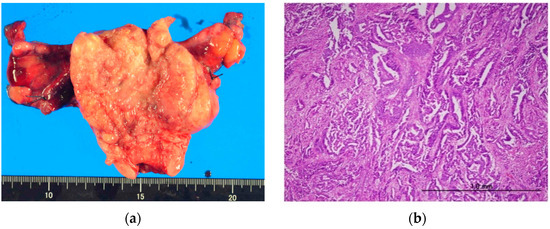

2. Case Presentation